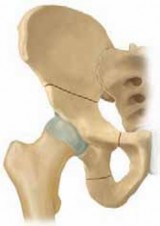

Chapter 74 Chiari Medial Displacement Osteotomy of the Pelvis Travis H. Matheney and Brian Snyder DEFINITION …

Chapter 73 Triple Innominate Osteotomy Dennis R. Wenger and Maya E. Pring DEFINITION Triple innominate osteot…

Chapter 67 Anterior Approach for Open Reduction of the Developmentally Dislocated Hip Richard M. Schwend DE…